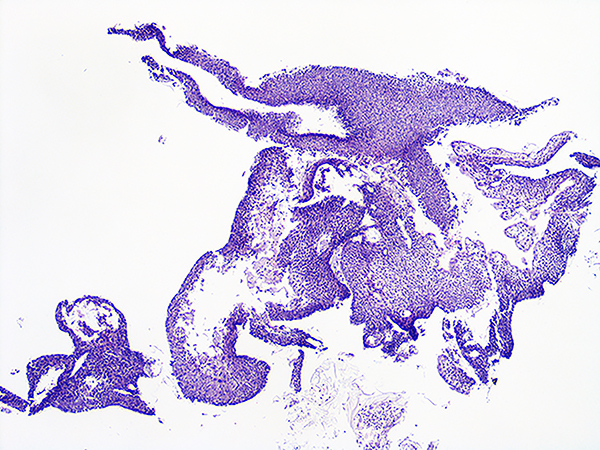

Case 1

Soft Bx CIN 2 10x - Low Power